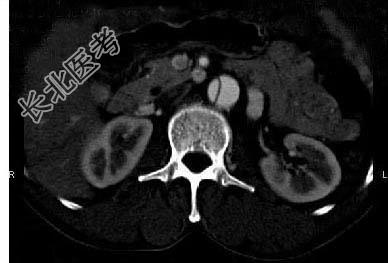

- 多项选择题请看一组主动脉的CT增强图像,正确的描述和结论是 ( )

A、主动脉血栓

B、主动脉瘤

C、主动脉夹层

D、真腔较假腔小

E、真假腔之间线状低密度影为内膜片影